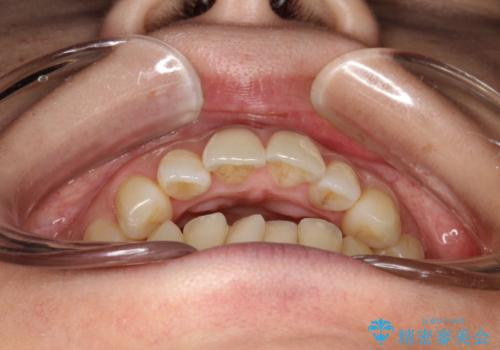

- 出っ歯で口が閉じずらくて、前歯でものかが噛み切れないとのことで来院されました。

上顎の前歯が前方に傾斜して、下顎の前歯と接触していない状態でした。

上顎の前から4番目の歯を両側抜歯して前歯を後方に移動させる計画としました。

前歯がしっかり下がることで、上下の前歯があわさり食事もしやすくなったと言っていただきました。